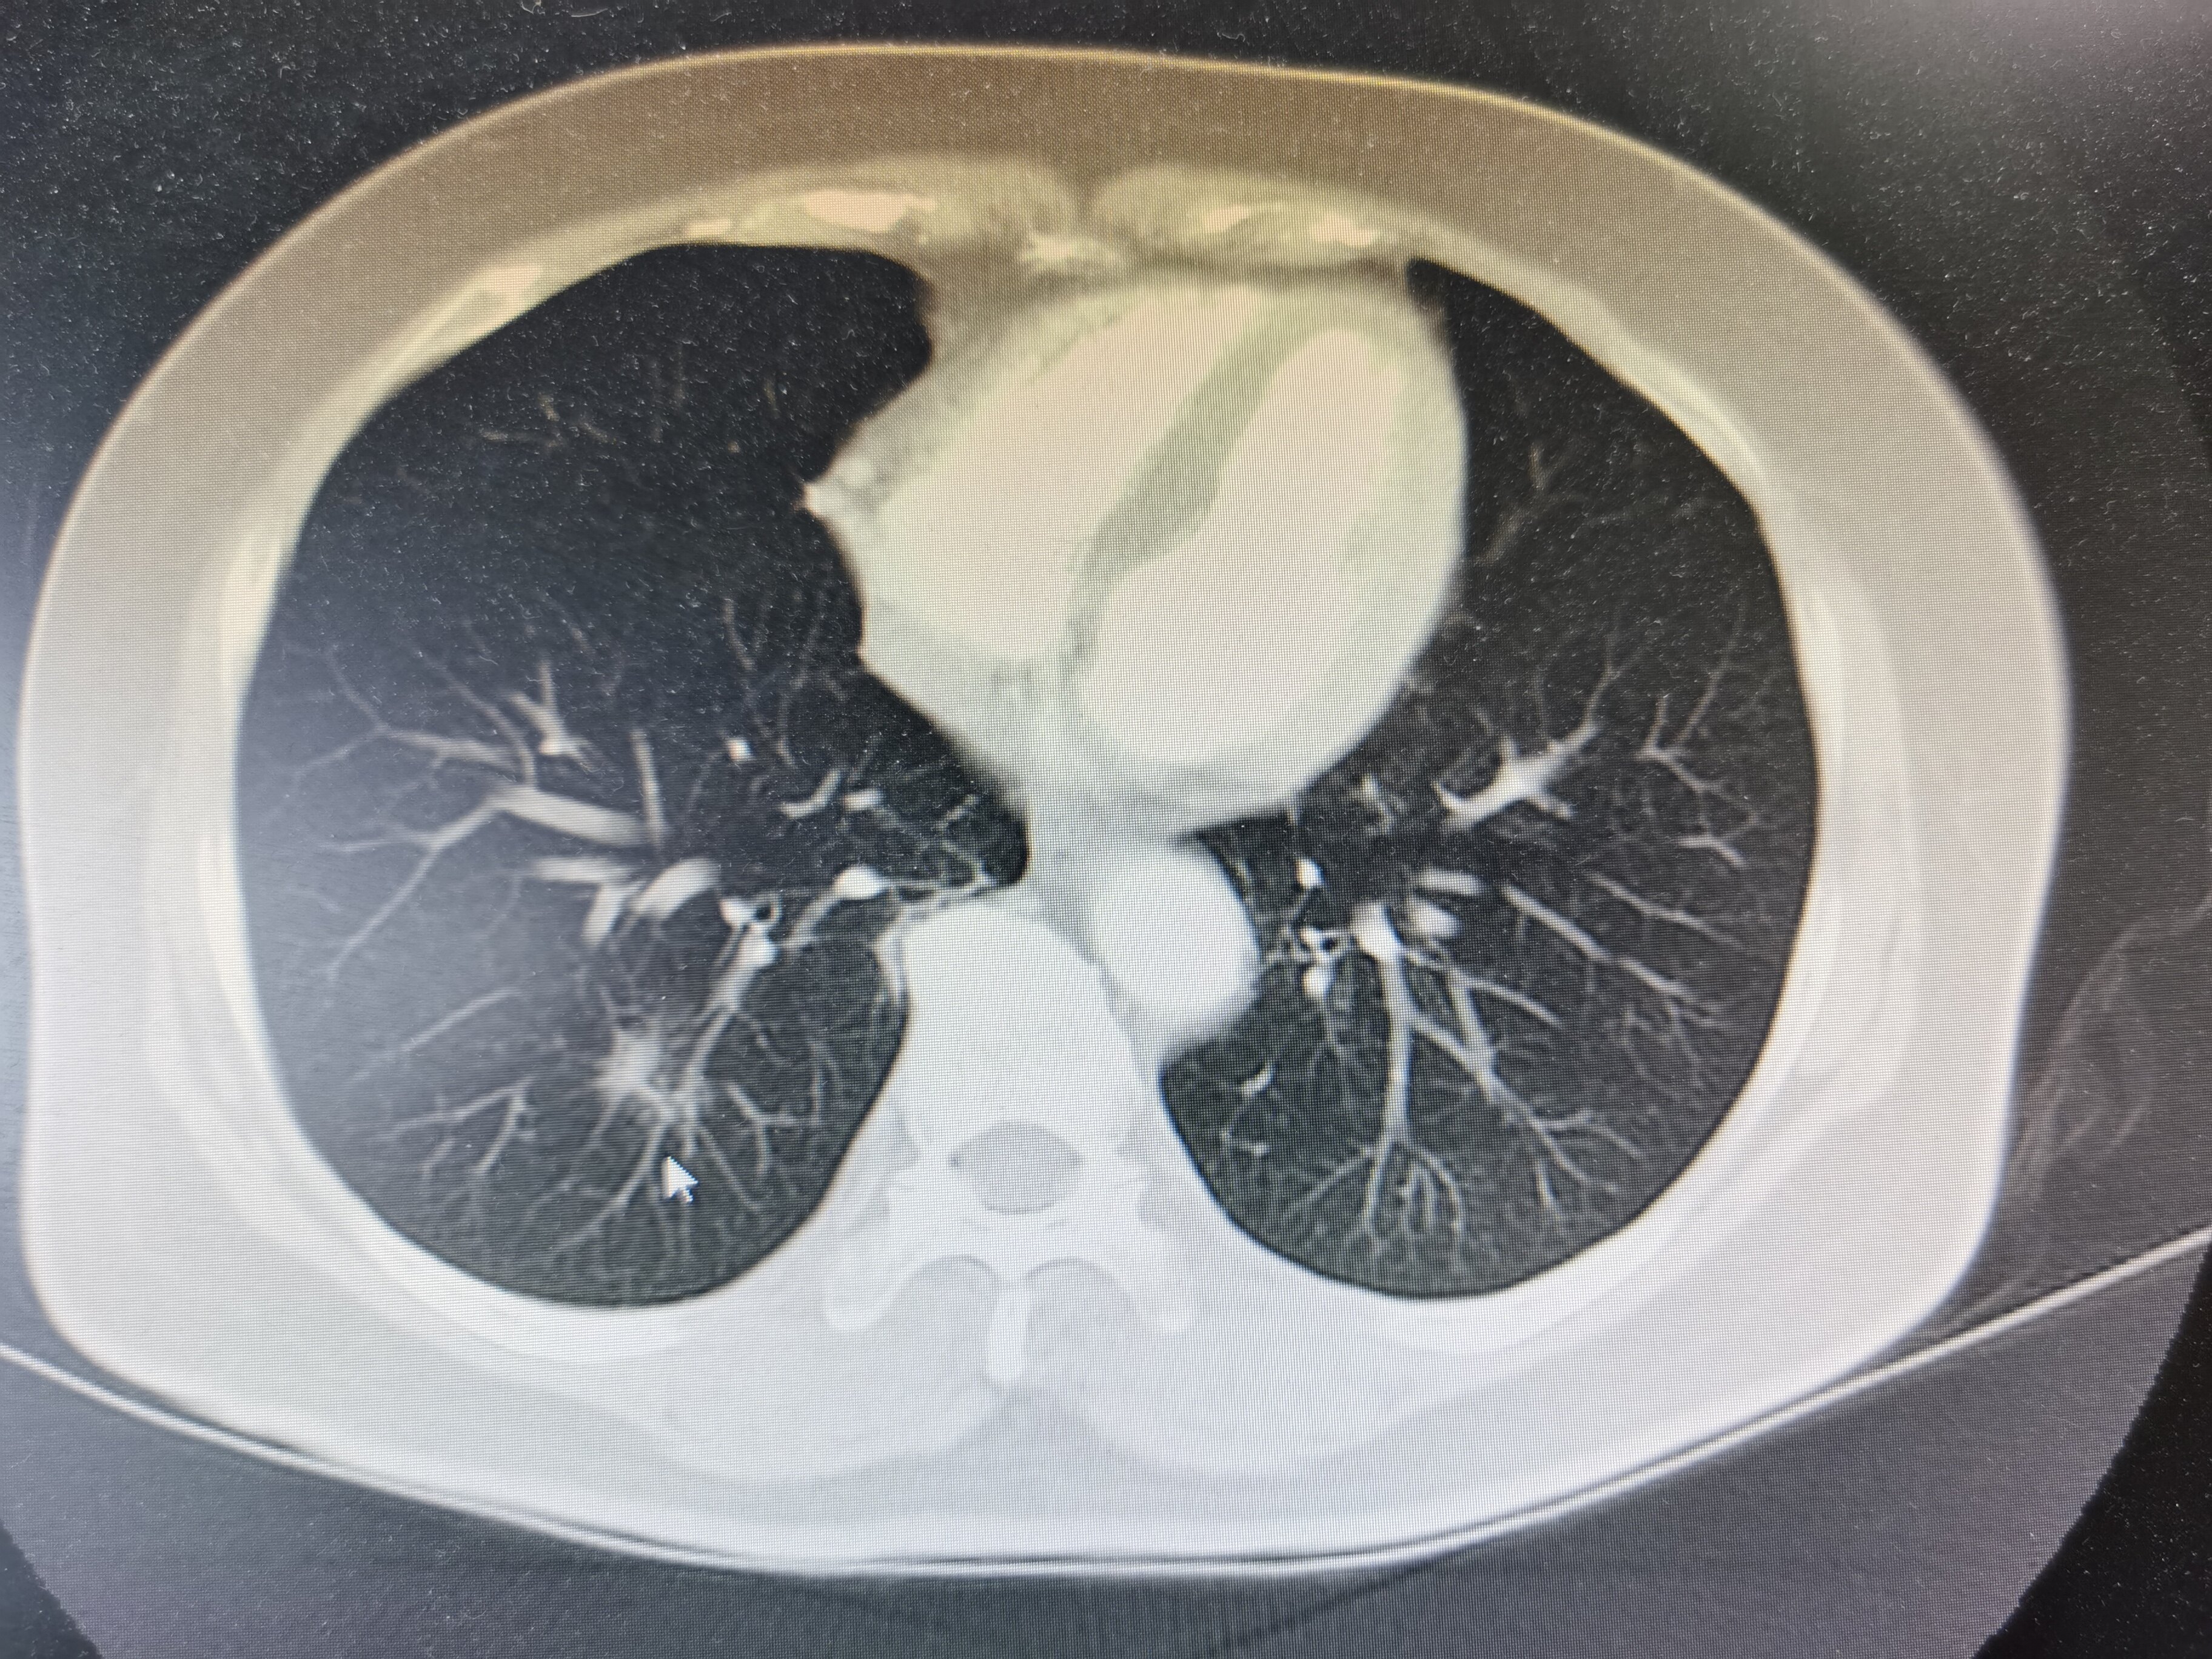

在胸部CT上发现了肺部结节,应该详细评估胸部CT的特征以及患者疾病的特点,有无肺癌家族史、有无长期吸烟等,根据相关情况进行综合分析,然后给予相应的处理。